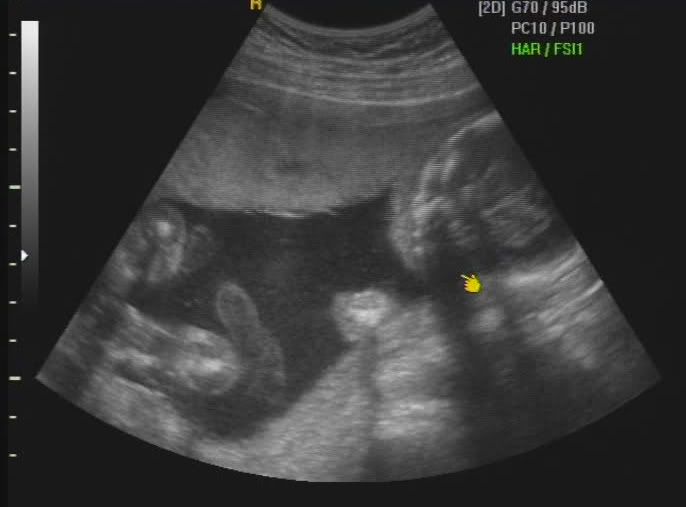

Hola a todos!, me presentaría, pero todavia no he nacido y no tengo nombre, se supone que lo haré aproximadamente el 26 de Marzo, mis papis (Dinís y Bárbara) acaban de enterarse de que voy a ser una niñita y están pensando en que nombre ponerme, a ellos les gustaría un nombre compuesto ya que es tradición en sus dos familias, pero como tienen un lio del carajo he decidido abrir este blog primero para que les ayudeis con mi nombre, y después para que sigais mi evolución como bebecita.